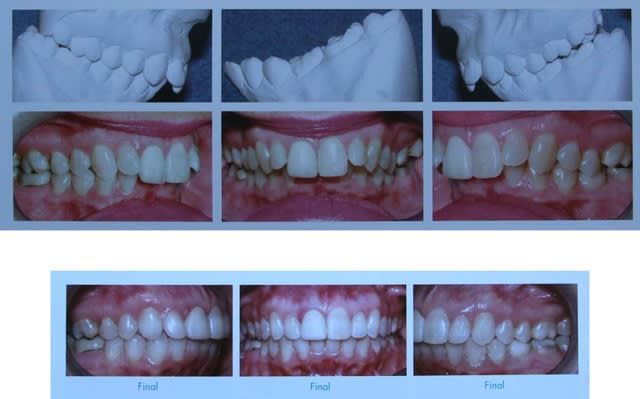

Vous vous rappelez de ce cas Damon ?

Image 1 qf9ljh - Eugenol

Voici un cas esthétique

Sans élastiques

Je sens que je vais me faire remonter les bretelles

Si je vous dit : ne la trouvez vous pas plus belle.

Voici les Rx. de ses ossements

Et les photos d’antan.

Un traitement doux et sans frictions

Mais avec une contention

Image 1 t4kxzx - Eugenol

Image 2 zgsvvq - Eugenol

Image 3 a1rigo - Eugenol